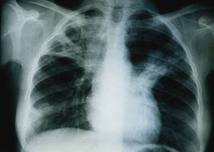

WASHINGTON, 17 oct 2012 (AFP) - La tuberculose, qui a tué 1,4 million de personnes en 2011, continue à reculer mais le combat contre la maladie "reste fragile" notamment en terme de financement, a annoncé mercredi l'Organisation mondiale de la santé.

La tuberculose reste "la principale maladie infectieuse mortelle aujourd'hui", souligne l'OMS.